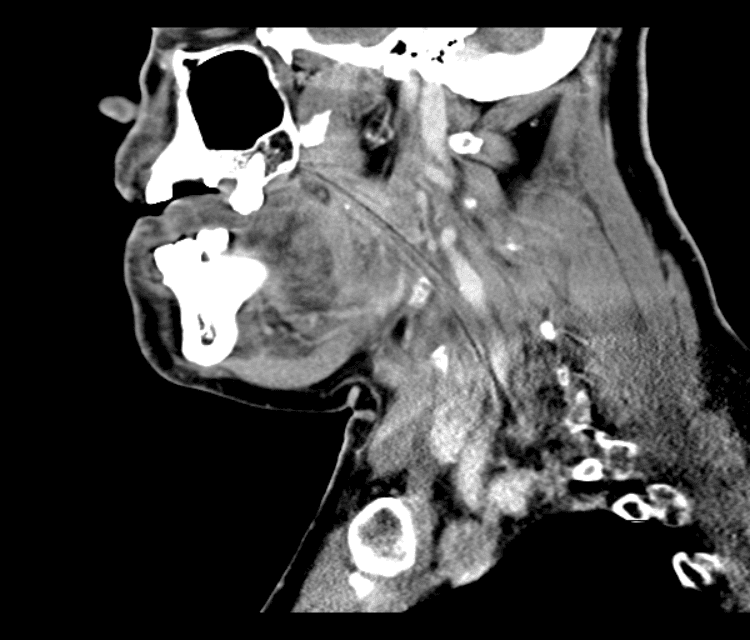

Head and Neck

Simulates call by including subtle or difficult cases and some normals.